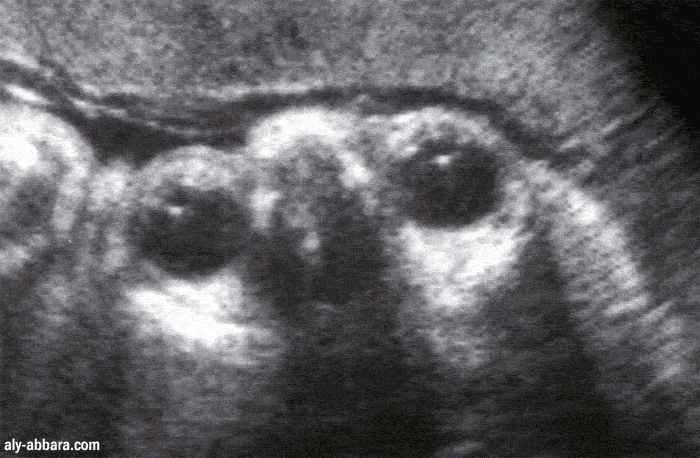

Globes oculaires fœtaux à 32 SA

Aspect échographique permettant d'identifier les principaux éléments anatomiques de œil :

cristallins et leurs ligaments, humeurs aqueuses, corps vitrés et les structures osseuses des orbites oculaires